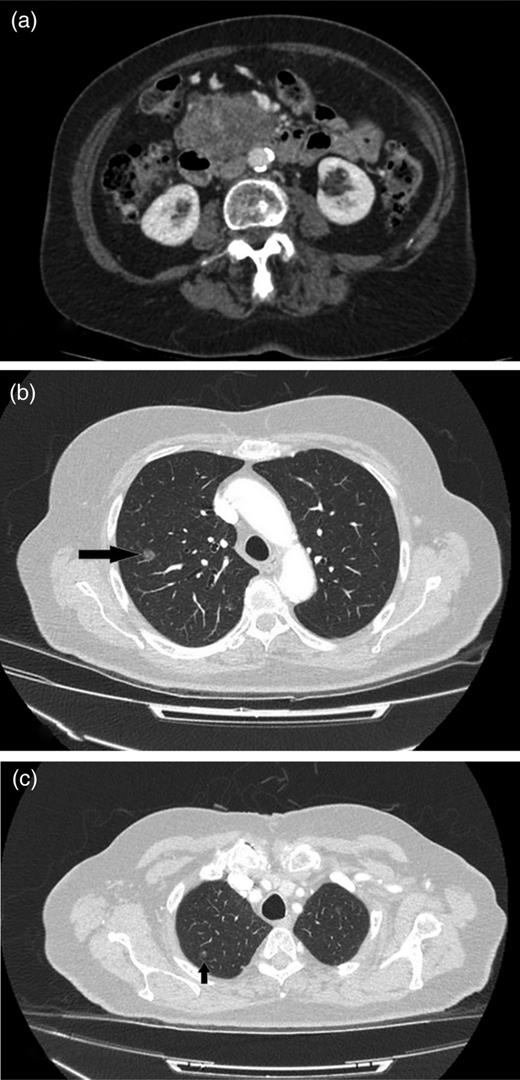

Following the histological findings, a CT of her thorax, abdomen and pelvis was arranged (Fig. 2). The CT scan reported a large solid cystic mass in the uncinate process of the pancreas measuring 7.2 cm × 4.8 cm in the axial dimension and 7.2 cm in the coronal dimension (Fig. 3). There was displacement of the superior mesenteric vein and artery but no vascular invasion. The CT scan also confirmed lung lesions consistent with metastatic disease (Fig. 3b and c).

(a) CT image of 2015, a mass lesion in the head of the pancreas with solid and cystic components (bunch of grapes appearance). The lesion measures 7.2 × 4.8 cm in the axial dimension and 7.2 cm in the coronal dimension. (b and c) Multiple focal ground-glass density nodules in both upper lobes of the lungs, largest measuring 1 cm in the right upper lobe.